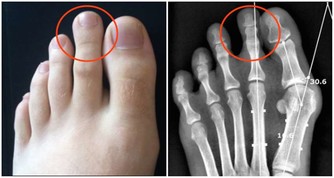

5 搓腳:排毒延壽

“三里湧泉穴,長壽妙中訣。睡前按百次,健脾益精血。”

睡前花幾分鐘時間按摩湧泉穴,不僅可治療糖尿病、更年期障礙、

多眠症、暈眩、高血壓、焦躁、過敏性鼻炎、腎髒病等多種疾病,還可以排毒養腎。